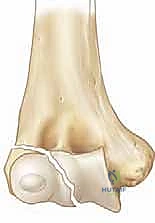

A profound, three-dimensional understanding of the distal humerus and its enveloping soft tissue envelope is paramount for successful surgical intervention. The lateral condyle is a complex, multi-tissue structure comprising the capitellum (the primary hemispherical articulation with the radial head) and a significant portion of the lateral metaphysis. Proximally, these fracture lines almost invariably originate in the posterolateral metaphysis. The fracture then propagates distally along the physis (the growth plate) before taking an abrupt turn to exit through the epiphysis.

The precise location where the fracture line exits the epiphysis forms the basis of the classic Milch classification, which has profound biomechanical implications. In a Milch Type I fracture, the line traverses the metaphysis and physis, then extends directly across the ossific nucleus of the capitellum. This is functionally analogous to a Salter-Harris type IV fracture. While less common, it strictly involves the lateral aspect of the joint. In contrast, the much more common Milch Type II fracture extends from the metaphysis, travels along the physis, and exits medially through the unossified trochlear groove, medial to the capitellar ossification center.

The Milch Type II pattern is inherently and significantly more unstable. By exiting through the apex of the trochlea, the fracture effectively destabilizes the lateral trochlear ridge. This ridge is the primary osseous buttress preventing lateral translation of the radioulnar complex. When this buttress is compromised, the entire forearm is permitted to subluxate laterally, carrying the fractured condylar fragment with it. Radiographically, a Milch Type II may deceptively resemble a Salter-Harris type II injury, but its intra-articular extension makes it functionally akin to a Salter-Harris type III or IV, demanding meticulous anatomical reduction.

Clinical & Radiographic Imaging Archive